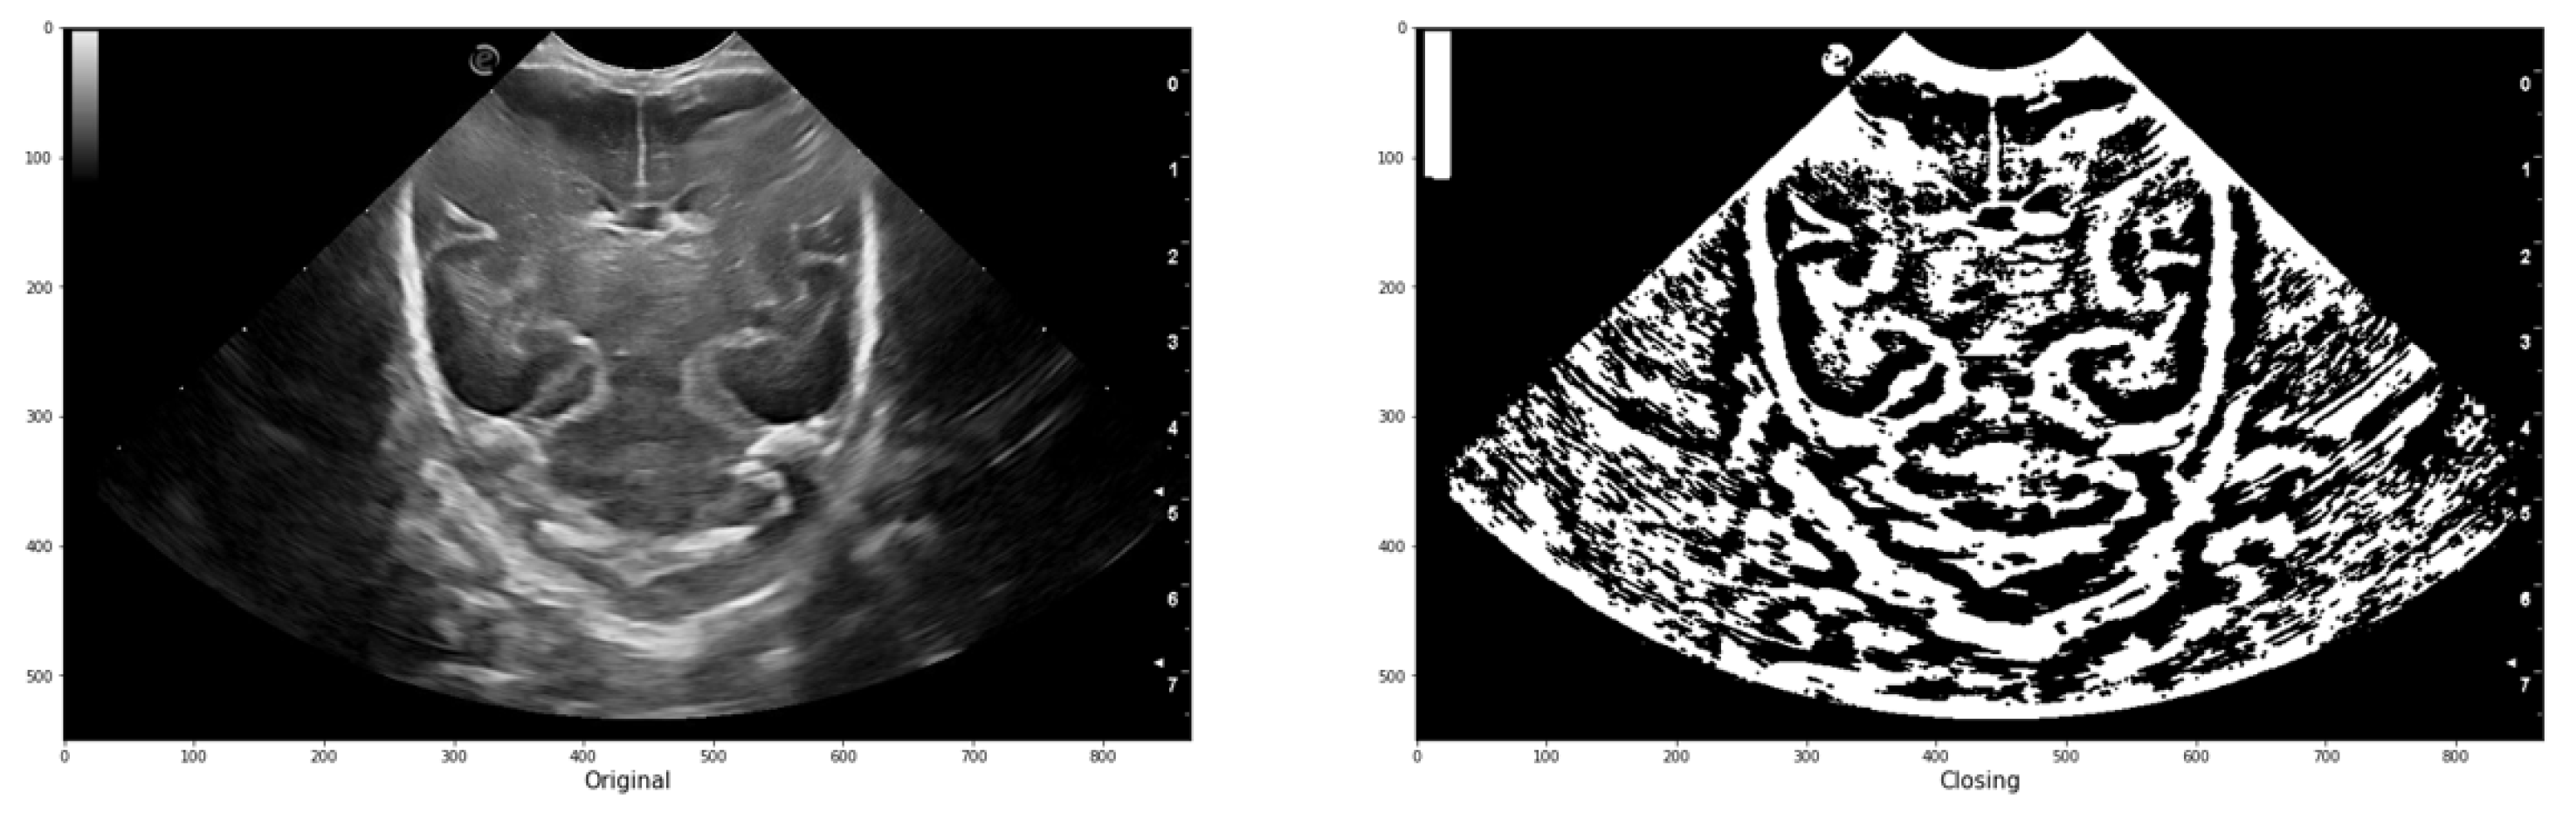

In image processing, erosion reduces bright regions and enlarges dark regions by setting the pixel value at (i, j) to the minimum over all pixels in the neighborhood centered at (i, j). Conversely, dilation enlarges bright regions and reduces dark regions by setting the pixel value at (i, j) to the maximum over all pixels in the neighborhood centered at (i, j). In the platform, both operations are used in a function called "closing" represented by Equation 5. This function performs greyscale morphological closure of an image by applying dilation followed by erosion. It effectively removes small dark spots and connects small bright cracks. This operation is useful for closing dark spaces between bright features in the image. The function takes the image and the trace (expressed as a matrix of ones and zeros) as parameters.

Figure 8 illustrates an example of the application, demonstrating how a group of initially connected structures is merged together to achieve a segmentation result that closely resembles the intended structure.

Figure 8. Example of an original image and the resulting image after applying a threshold and closure function for comparison.